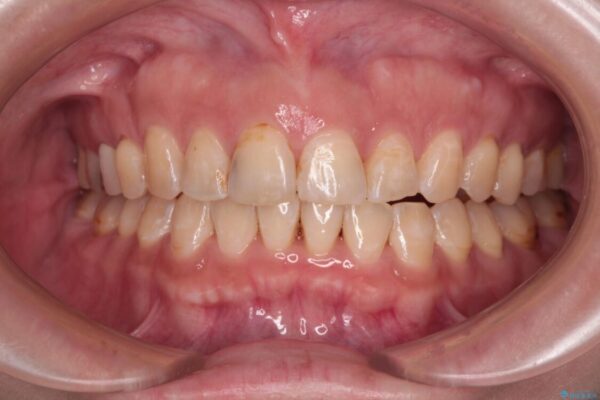

治療後について

舌の突出癖が原因で上下の歯に大きなスペースが生じていたため、舌のトレーニングをしっかり行っていただくことで、上顎歯列をスムーズに移動させることができました。

治療後